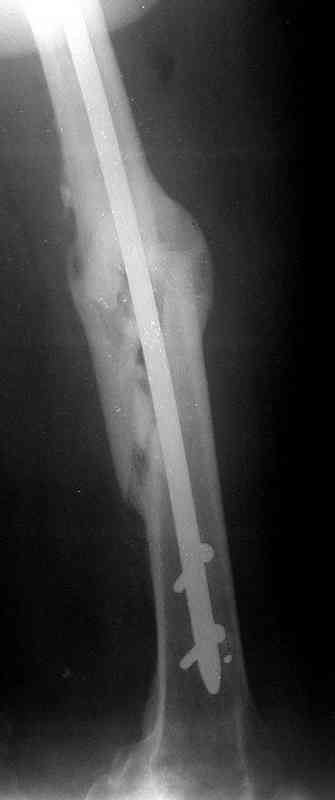

месяцев дистракции укорочение левого бедра удалось полностью устранить. 22.02.00, т.е. через 2 месяца после повторного остеосинтеза, больному произведено дистальное блокирование штифта двумя винтами и демонтирован аппарат Илизарова. В течение 2 недель после операции больной ходил с помощью костылей, потом 2 недели с тростью. Опороспособность и функция оперированной конечности полностью восстановились через 4 недели после операции.

Фиксаторы удалены через 12 месяцев после операции, выполненной по поводу замедленной консолидации перелома бедра с его укорочением.